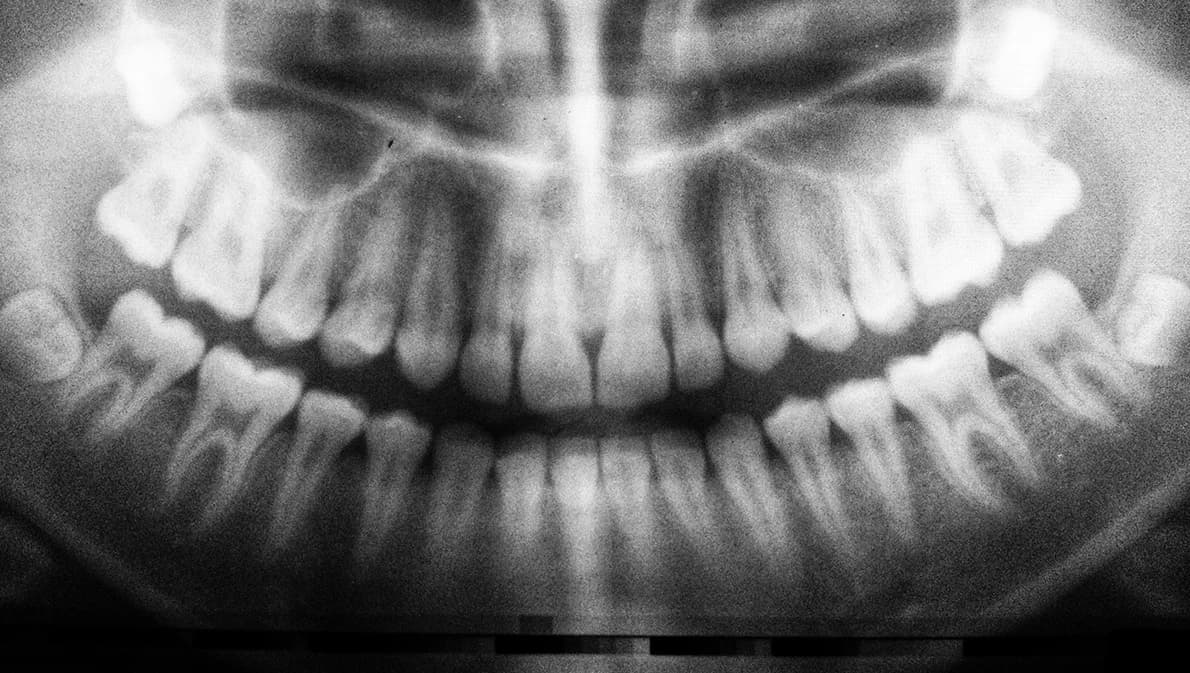

ก่อนสิ้นเดือนธันวาคมนี้ ผู้ประกันตนมาตรา 33 และมาตรา 39 อย่าลืมใช้สิทธิ ‘ทำฟัน’ ประจำปี 65 วงเงิน 900 บาท ไม่ต้องสำรองจ่าย สามารถทำทันตกรรมได้ทั้งขูดหินปูน อุดฟัน ถอนฟัน และผ่าฟันคุด

ทั้งนี้ บริการทำฟันที่ผู้ประกันตนสามารถเข้ารับบริการได้ ได้แก่ ขูดหินปูน อุดฟัน ถอนฟัน และผ่าฟันคุด โดยหากเข้ารับบริการที่คลินิกหรือสถานพยาบาลที่ค่ารักษาเกินงบ 900 บาท ผู้ประกันตนจะต้องจ่ายเงินส่วนเกินดังกล่าว ส่วนเงื่อนไขของการใช้สิทธิได้นั้น จะต้องเป็นผู้ประกันตนที่ส่งเงินสมทบมาแล้วครบ 3 เดือน ภายในระยะเวลา 15 เดือน ก่อนวันรับบริการ และหากได้ลาออกจากงานแล้ว ก็ยังสามารถรับบริการทำฟันภายในเวลา 6 เดือนหลังการลาออกได้เช่นกัน